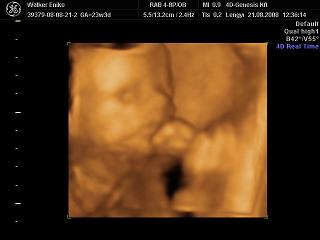

Nagyon helyesek a 4D-s fotók!!!